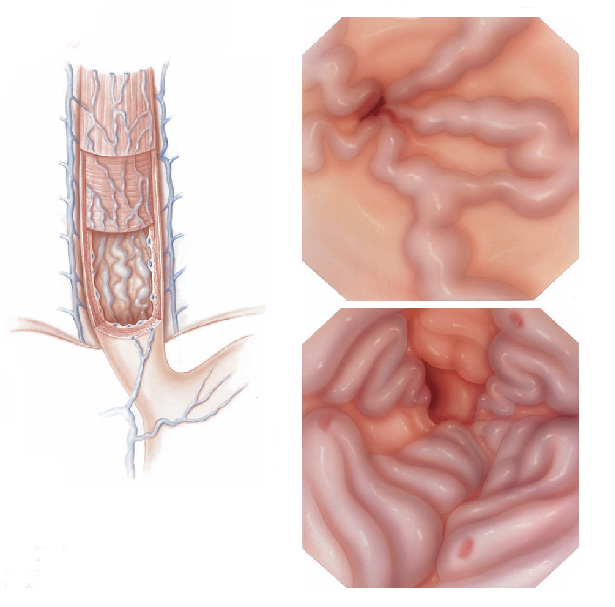

É um exame indicado para avaliação diagnóstica e tratamento das doenças da parte superior do tubo digestivo, incluindo o esôfago, o estômago e a porção inicial do duodeno.

Realizado introduzindo-se pela boca um aparelho flexível com iluminação central que permite a visualização de todo o trajeto examinado.

Colonoscopia é o exame endoscópico do cólon (intestino grosso) e muitas vezes também do íleo terminal (porção final do intestino delgado). Além da inspeção da superfície intestinal, a colonoscopia permite também a realização de biópsias que podem ser úteis no estabelecimento do diagnóstico. Procedimentos terapêuticos também podem ser realizados durante a colonoscopia, entre eles o mais frequente é a remoção de pólipos (polipectomia).

O que acontecerá durante o exame ?

Após o preparo do cólon, o paciente é levado à sala de exame onde será sedado. A sedação é realizada por via endovenosa e ajuda o paciente a dormir e relaxar. O colonoscópio é então introduzido pelo reto até o ceco (porção inicial do cólon) ou até o íleo terminal (porção final do intestino delgado). Durante a retirada do aparelho é feita uma minuciosa inspeção identificando as eventuais alterações.

Colonoscopia é o exame endoscópico do cólon (intestino grosso) e muitas vezes também do íleo terminal (porção final do intestino delgado). Além da inspeção da superfície intestinal, a colonoscopia permite também a realização de biópsias que podem ser úteis no estabelecimento do diagnóstico. Procedimentos terapêuticos também podem ser realizados durante a colonoscopia, entre eles o mais frequente é a remoção de pólipos (polipectomia).

O que acontecerá durante o exame ?

Após o preparo do cólon, o paciente é levado à sala de exame onde será sedado. A sedação é realizada por via endovenosa e ajuda o paciente a dormir e relaxar. O colonoscópio é então introduzido pelo reto até o ceco (porção inicial do cólon) ou até o íleo terminal (porção final do intestino delgado). Durante a retirada do aparelho é feita uma minuciosa inspeção identificando as eventuais alterações.